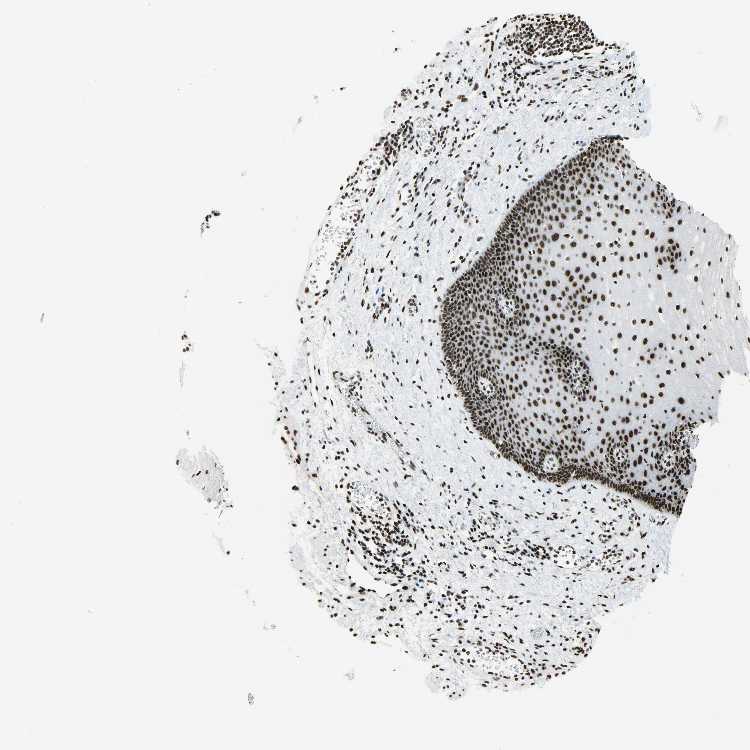

ESOPHAGUS - Antibody stainingi

Antibody staining in the annotated cell types in the current human tissue is reported as not detected, low, medium, or high, based on conventional immunohistochemistry profiling in selected tissues. This score is based on the combination of the staining intensity and fraction of stained cells.

Each image is clickable and will lead to virtual microscopy that enables deeper exploration of all samples and also displays staining intensity scores, fraction scores and subcellular localization as well as patient and tissue information for each sample.

Antibody HPA046440Antibody CAB004652

Squamous epithelial cells MediumHigh